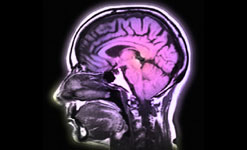

Psychologists Matthew Lieberman and Naomi Eisenberger at the University of California in Los Angeles have been investigating what happens in the brain when a person is socially rejected.

Their experiment involved putting people in a functional Magnetic Resonance Imaging brain scanner as they played a computer game with what they imaged were two other players. During the game, the other players stopped including them in the game. The researchers monitored what happened in the brains of the rejected.